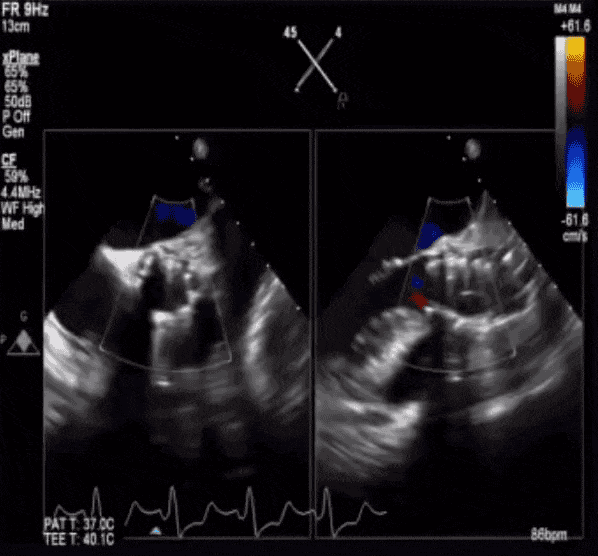

患者为71岁女性,影像学检查提示三叶式主动脉瓣,瓣膜增厚钙化,开放重度受限,钙化积分HU850:722mm³,主动脉瓣口面积仅为0.7 cm²,平均跨瓣压差53 mmHg,主动脉瓣口峰值流速高达4.6 m/s,诊断为主动脉重度狭窄。葛均波院士亲自携多学科团队进行评估并制定了详细的手术方案,拟采用20 mm球囊进行预扩,植入AV26TaurusNXT主动脉瓣。术中通过多次使用回收功能寻找最理想的锚定位置和释放位点,并使用22mm 球囊进行后扩张。术后即刻经食道超声心动图评估显示仅微量瓣周漏,平均跨瓣压差仅为7 mmHg,主动脉瓣口峰值流速为1.9 m/s,术后即刻瓣口面积为2.0cm²,血流动力学指标理想。

TaurusNXT植入过程:

瓣膜稳定释放

术后即刻造影